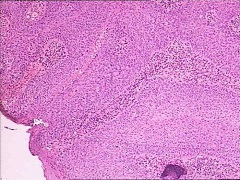

2、基底细胞癌

起病时常无症状,初期多为基底较硬斑块状丘疹,有的呈疣状隆起,而后破溃为溃疡灶改变,不规则,边缘隆起,似火山口,底部凹凸不平,生长缓慢。转移者极少,先发生边缘半透明结节隆起浅在溃疡,继之渐扩大,可侵蚀周边组织及器官,成为侵蚀性溃疡。